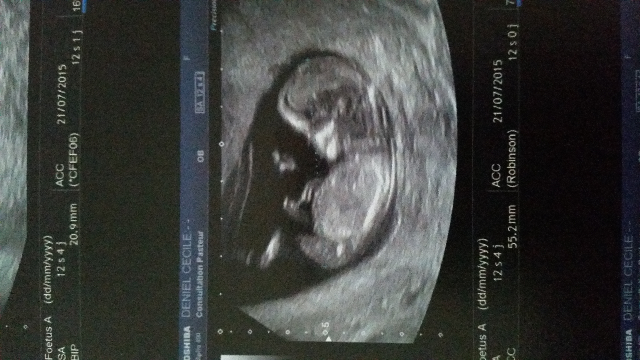

bébé été 2015